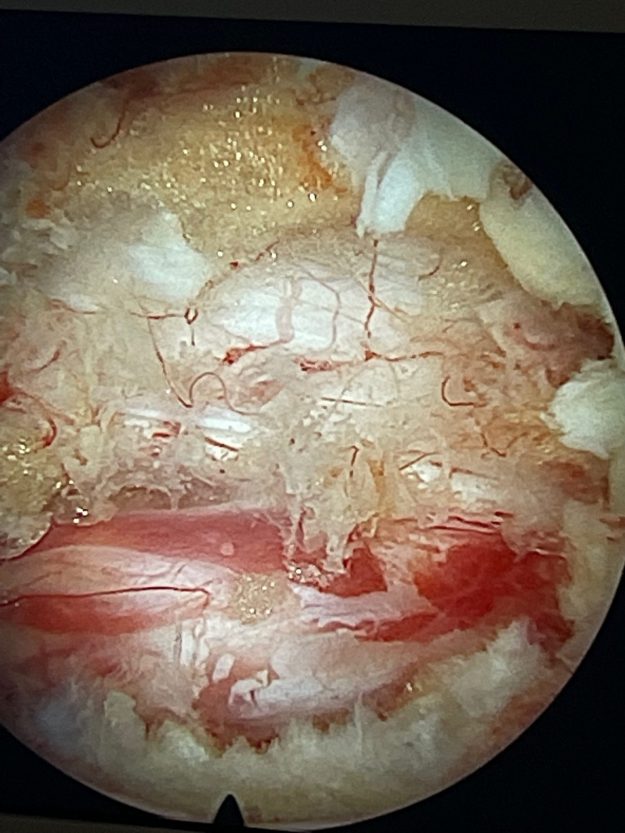

Νεαρή ασθενής 17 ετών με εκτεταμένη συριγγομυελία από την αυχενοπρομηκική συμβολή έως το τελικό τμήμα του νωτιαίου μυελού, λόγω συνδρόμου Chiari. Κλινικά αιμωδίες (μουδιάσματα) άνω άκρων, ζάλη. Αφού ο εργαστηριακός έλεγχος απέκλεισε συνοδά προβλήματα (πχ καθηλωμένο τελικό νημάτιο κ.α.) αποφασίστηκε η επέμβαση αποσυμφόρησης του οπισθίου κρανιακού βόθρου με ανάδυση των αμυγδαλών της παρεγκεφαλίδας και μηνιγγοπλαστική.…